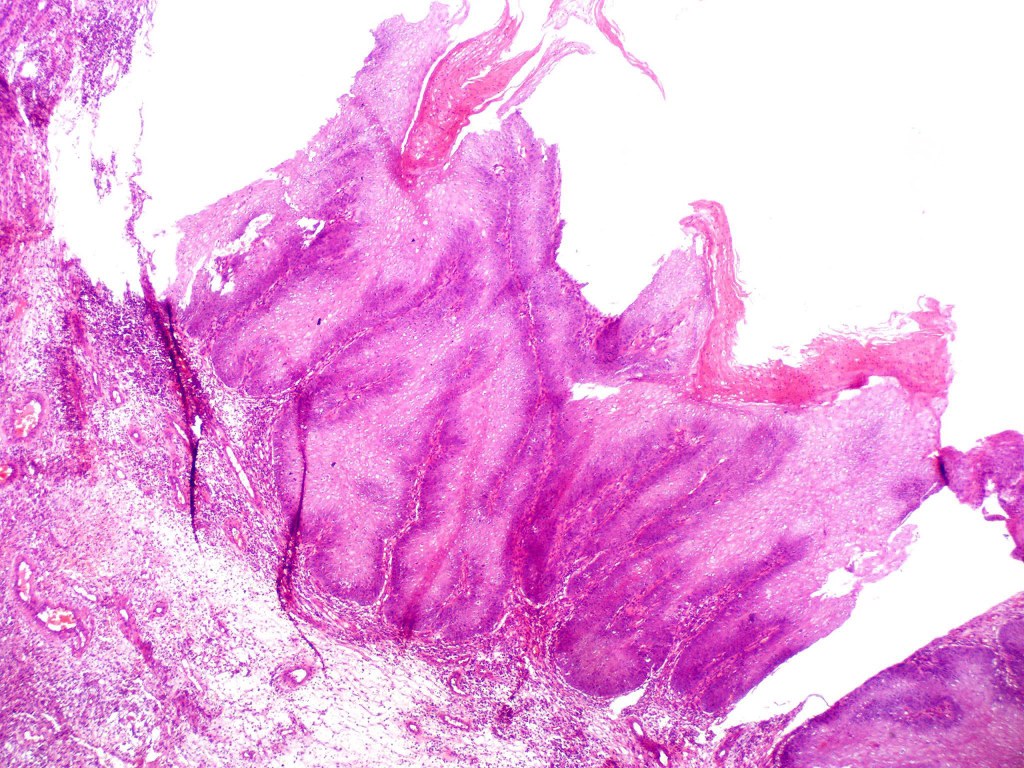

•Often massive hyperkeratosis

•Epidermal verrucous hyperplasia

•Deeply penetrating bulbous processes with a pushing rather than infiltrating lower border